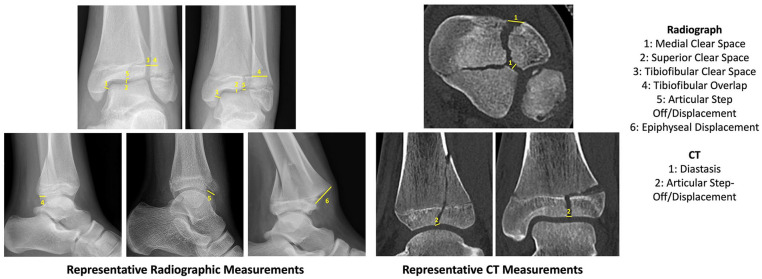

Results: A total of 61 patients were included in this study. The average age of patients was 12.3, and 65.6% of patients were male. There was an almost even split of triplane (55.7%) and Tillaux (44.3%) fractures. Overall, measurements showed at least good interobserver agreement (ICC >0.6). Radiographic anteroposterior view showed the least reliable measurements compared to the mortise and lateral views. There was significant correlation between CT displacement and the following measures on radiographs: tibiofibular clear space on the mortise view (ρ = 0.27, p < 0.05), articular displacement on the mortise view (ρ = 0.35, p < 0.01), articular displacement on the lateral view (ρ = 0.28, p < 0.05), and epiphyseal displacement on the lateral view (ρ = 0.55, p < 0.001).

Conclusions: There are several radiographic parameters that significantly correlate with increased displacement of transitional ankle fractures on CT. Increased articular displacement on the mortise and lateral view, as well as increased tibiofibular clear space on the mortise view, correlates with increased displacement. These radiographic parameters may be good indicators for the selective use of CT scans for transitional ankle fractures.